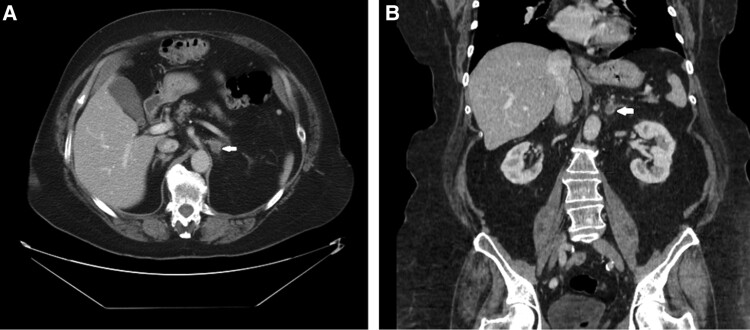

Adrenal adenomas are benign tumors of the adrenal cortex that may secrete excess hormones, such as cortisol. They are most commonly discovered during imaging studies for unrelated problems. Lipomatous metaplasia is a rare degenerative change in adrenal adenomas, characterized by the presence of adipose tissue and hematopoietic elements within the tumor. In this report, we present a case of an adrenal adenoma with lipomatous metaplasia in a patient with hypertension, hyperlipidemia, and type II diabetes mellitus. The discovery of this adrenal mass was prompted by an evaluation of the patient's progressive hirsutism. The tumor was found to be secreting cortisol, leading to Cushing syndrome. The patient subsequently underwent surgical resection of the mass after being treated with mifepristone. The histopathological examination confirmed it to be an adrenal cortical neoplasm with lipomatous metaplasia, characterized by uncertain malignant potential. The patient did well postoperatively. Three months after left adrenalectomy, the patient's hirsutism, A1c, and hypertension improved, allowing a reduction in antihypertensives. Her body mass index stabilized, her triglyceride decreased, and her dehydroepiandrosterone sulfate level normalized. She continued to do well at follow-up visits. Overall, this was a rare case of a functioning adrenal adenoma with lipomatous metaplasia, presenting both diagnostic and therapeutic challenges.